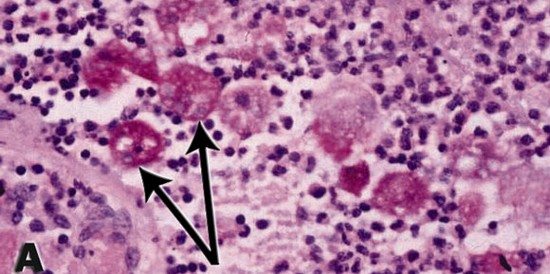

akut barsak enfeksiyonlari